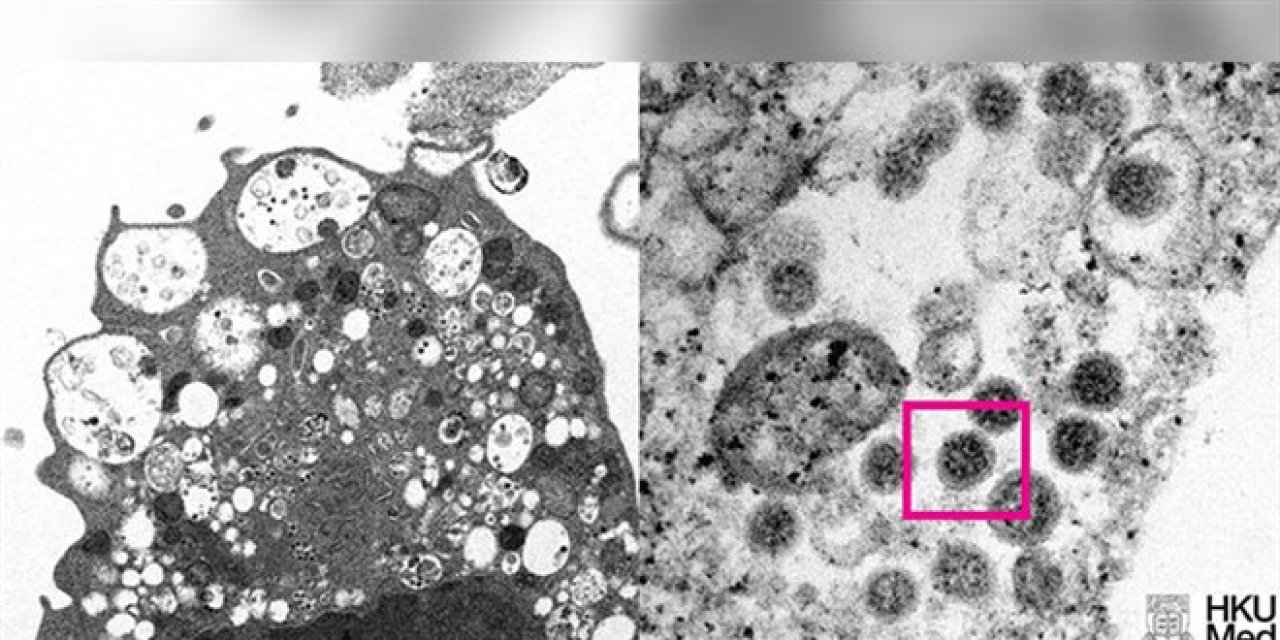

Omicron varyantının elektron mikroskobu görüntüsü yayınlandı